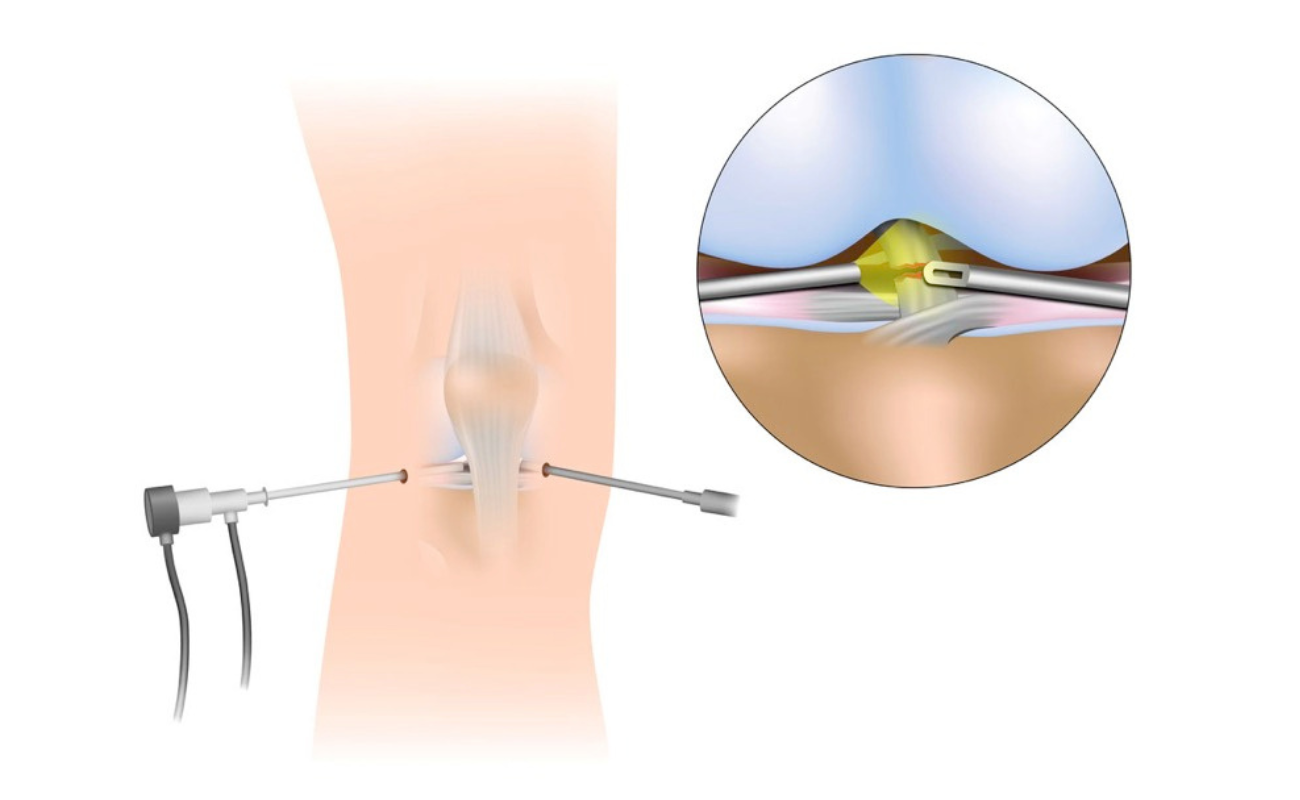

Recovery from Hip Replacement Surgery: A Comprehensive Guide

Today, hip replacement surgery has become one of the most commonly performed surgeries, with more than 300,000 procedures done annually in the U.S. alone.

A Guide to Hip Replacement Surgery: Types, Techniques, and Finding the Right Surgeon

Hip replacement surgery has revolutionized the treatment of hip pain and stiffness, offering a new lease on life for many individuals. If you're considering this

Start Here On Your Journey To Hip Wellness: Chennai's Best Surgeon

When it comes to entrusting someone with the health of your hips, finding the right surgeon is paramount. Chennai, renowned for its healthcare facilities

Transforming Healthcare: Robotic Hip-Replacement Surgery Trends in 2024

In 2024, the healthcare landscape in India is undergoing a remarkable transformation, particularly in the field of orthopedic surgery. Robotic hip-replacement surgery, a revolutionary advancement,

Why Some Patients May Need to Postpone Hip Replacement Surgery

Hip replacement surgery is a procedure that can relieve pain, restore mobility, and improve quality of life for patients with severe hip damage.